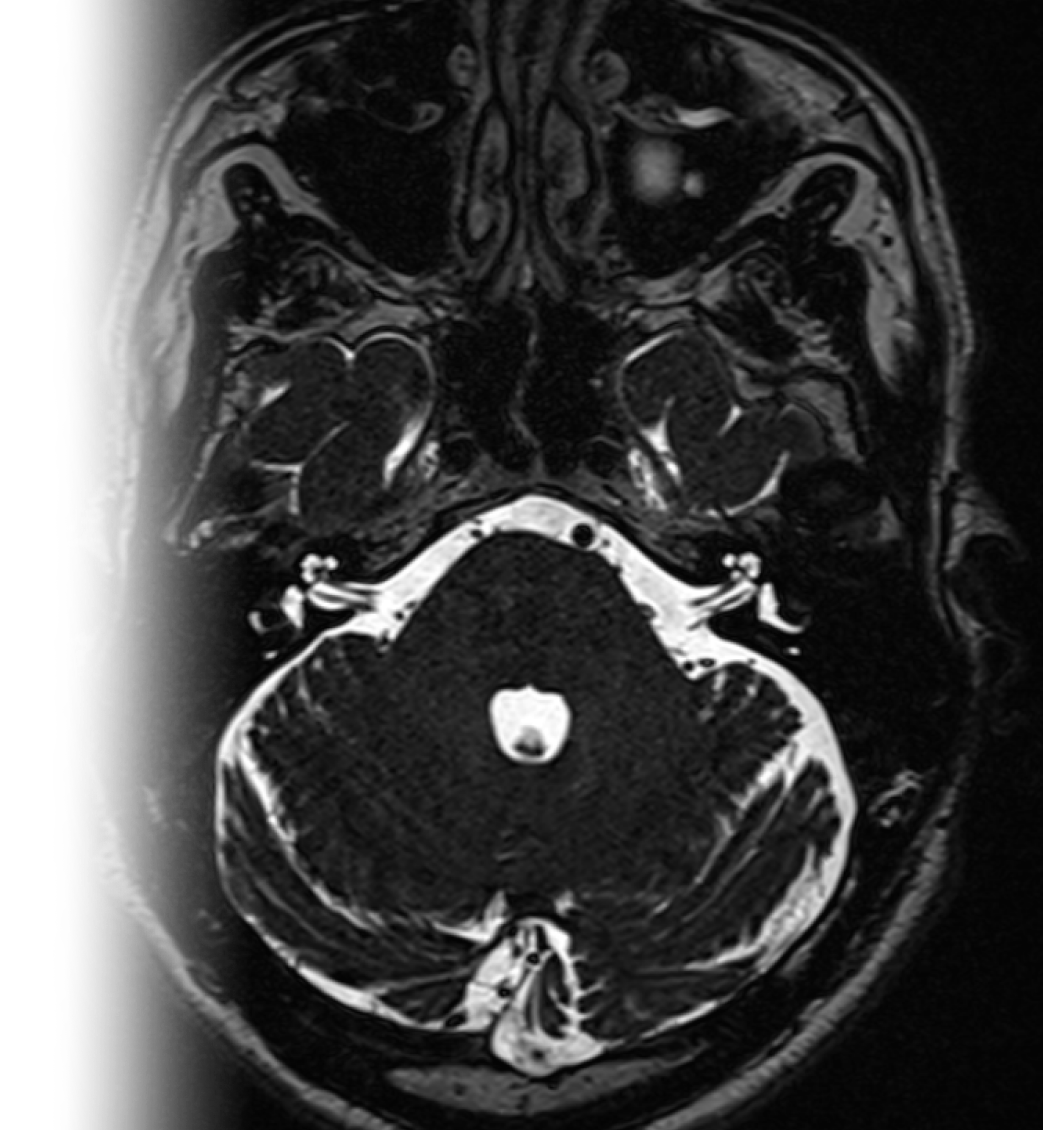

МРТ головного мозга при вазоневральном конфликте (тройничный нерв, вестибулокохлеарный нерв, мостомозжечковый угол) – важный метод исследования, который позволяет оценить структуры мосто-мозжечковых углов, взаимоотношения артерий и черепно-мозговых нервов.

78-1-1-020 МРТ головного мозга при вазоневральном конфликте (тройничный нерв, вестибулокохлеарный нерв, мостомозжечковый угол, запись на диск) 9 800 ₽